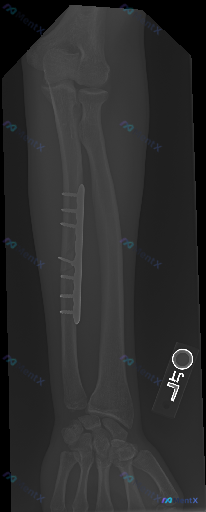

前臂正位X光片

- 尺骨:可见尺骨骨干处有内固定装置(钢板及螺钉)。钢板位于尺骨干处,通过多枚螺钉固定于骨皮质上。尺骨骨干可见陈旧性骨折愈合迹象,骨折线模糊,可见连续的骨痂形成影。

- 桡骨:桡骨骨干及干骺端骨皮质连续,未见明确的骨折线或骨质中断征象,骨皮质边缘光滑。

- 肘关节:肱尺关节、肱桡关节及上尺桡关节位置关系基本正常,关节间隙未见明显增宽或变窄。

- 腕关节:桡腕关节面平整,尺骨茎突与桡骨远端的对位关系未见明显异常。未见明显的脱位或半脱位征象。

- 骨质密度:尺骨及桡骨整体骨密度未见明显异常减低或增高。

- 骨小梁结构:骨小梁纹理清晰,走行自然,未见明确的溶骨性或成骨性破坏影,未见骨膜反应征象。

- 软组织:前臂软组织轮廓清晰,未见明显的异常肿胀或皮下气肿。

- 异物:影像显示存在金属内固定物(钢板及螺钉),除此以外,未见其他明显的金属、玻璃等高密度异物影。

- 图示骨骼发育成熟,未见明显的解剖变异。

这张片子的核心征象很明确:尺骨陈旧性骨折术后改变、内固定在位、伴骨痂形成。但在临床决策中,我们是否可以仅依据这张X光片就直接给出「正常愈合,继续随访」的结论?对于可能存在的「同影异病」风险,大家在阅片时会如何分层考虑优先级?欢迎先投票表达你的第一判断倾向,再回帖分享你的思考逻辑。